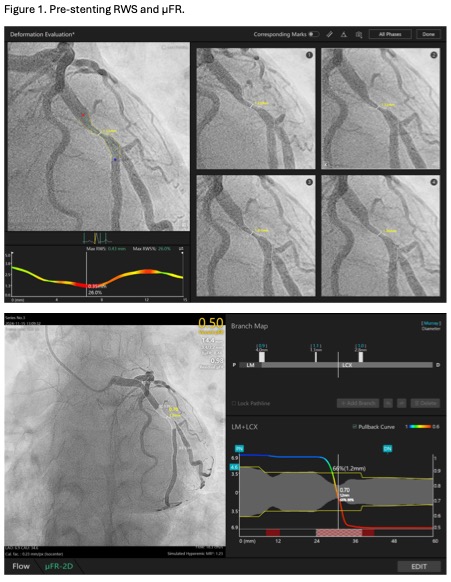

Coronary angiogram showed 90% stenosis of mid-LCX (Video 1). The maximum radial wall strain (RWS) was 26%, reflecting significant plaque vulnerability (>12%). Murray law-based quantitative flow ratio analysis (¥ìFR) was 0.50 (Figure 1), reflecting functional significance (<0.80). Optical coherence tomography (OCT) showed fibroatheroma with lipid arc of 270 degrees with mild calcification (Video 2). Overall, the findings were consistent with vulnerable plaque at mLCx.

A 6Fr EBU 3.5 guiding catheter was engaged into the left main using right radial access. Distal LCX was wired using Rinato. Pre-dilatation was done using a 4.0/15 NC Scoreflex scoring balloon. Freesolve¢ç 4.0/18 was implanted at 10atm. Post-dilatation was done using 4.5/15 Pantera Neo balloon. Results including stent expansion were excellent based on angiogram (Video 3) and OCT (Video 4). The post procedure RWS and ¥ìFR were 9.2% and 0.94, respectively (Figure 2).Six months later, we performed a restudy coronary angiogram for this patient, showing patent mLCX (Video 5), completely degraded resorbable scaffold and resolution of the vulnerable plaque on OCT (Video 6). The RWS and ¥ìFR were 0.37mm (11%) and 0.97, respectively (Figure 3). The patient remained asymptomatic.